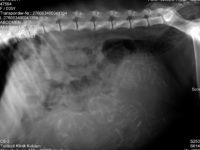

Heute Nachmittag waren wir – Berni, Crazy und ich, wieder in der Kleintierklinik Kotzian. Heute stand die Röntgenuntersuchung von Crazy auf dem Plan. Wie immer, wenn die Geburt näher rückt, ist etwas. Diesmal ist unserer Tierarzt, Dr.Kotzian Senior, leider krank. Zum Glück ist seine Praxis eine Klinik. Heute hat uns Dr. Skuballa betreut, da Dr. Kotzian Junior nur am Vormittag Dienst hatte. Wir sind heute im 58 Tag der Trächtigkeit. Nun kann mann die Skelette […]